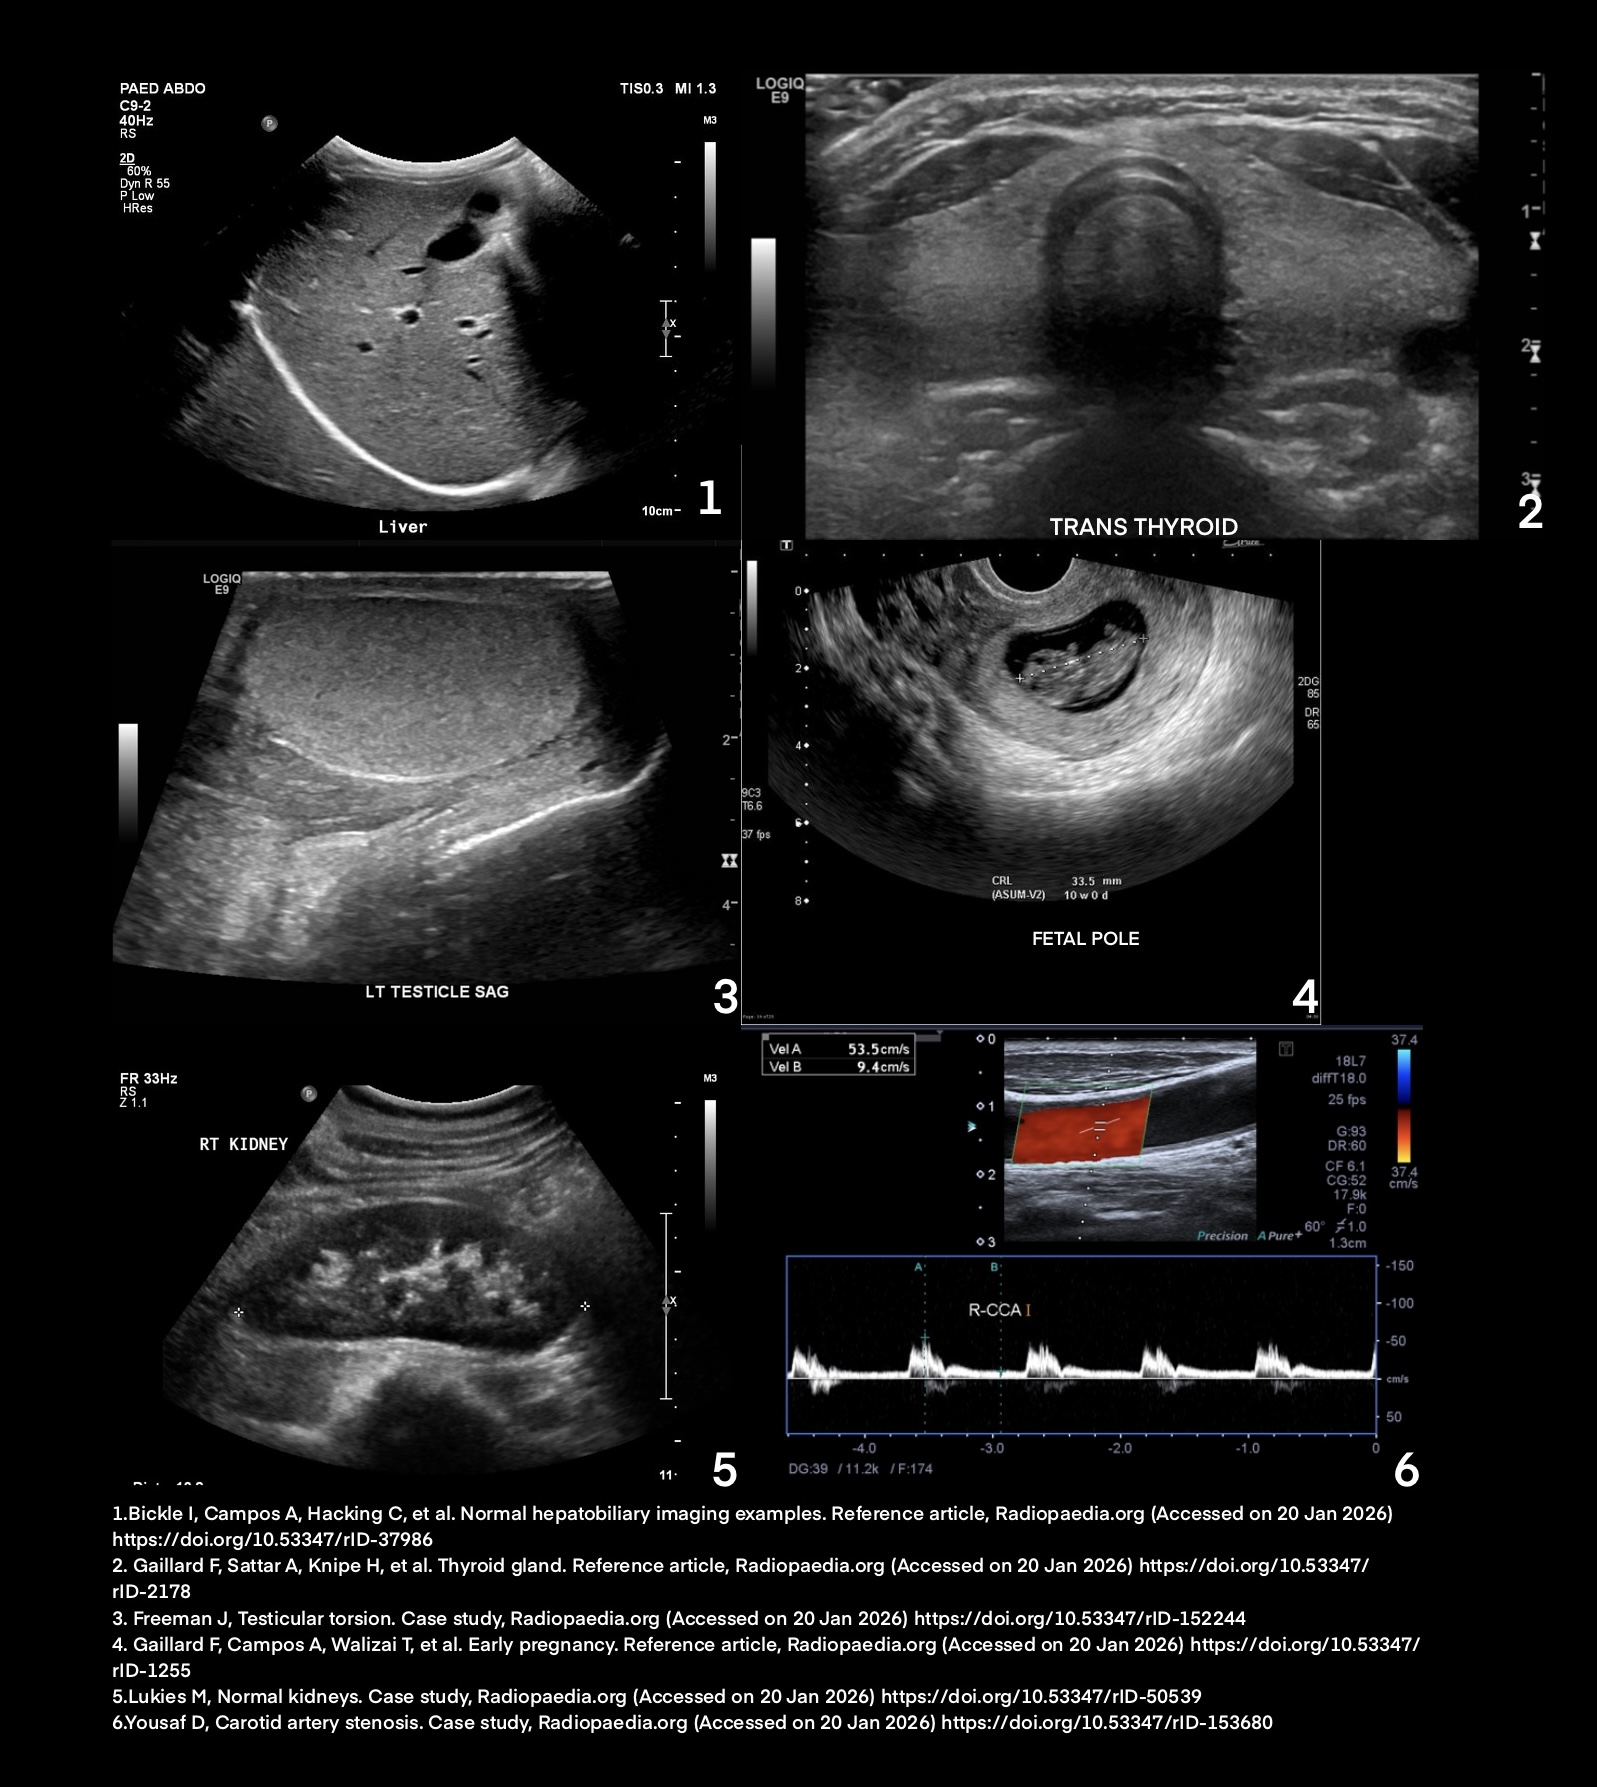

Diagnostic Medical Sonography, also known as ultrasound, is a non-invasive medical imaging technique that utilizes high-frequency sound waves to produce images of organs, tissues, or blood flow inside the body. These images are used to help diagnose and monitor various medical conditions; sonography is often the first imaging procedure performed when disease is suspected. Diagnostic medical sonographers are highly skilled professionals who work in hospitals, primary care clinics, and outpatient care centers.

- to utilize a non-invasive imaging modality to assist in the diagnosis and treatment of medical issues involving the female and male abdominal, urologic, gynecologic, obstetric, soft tissue, and cardiovascular systems

- to perform an investigative work-up that provides vital information, quantitative measurements, and differentiating findings in real-time to help determine a diagnosis, its severity, and develop treatment options for the patient